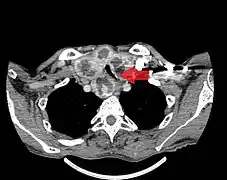

- Goitre comprimant la trachée cervicale.

Rétrécissement trachéal (flèche rouge). Tomodensitométrie (coupe transversale).

Même tumeur (coupe sagittale).